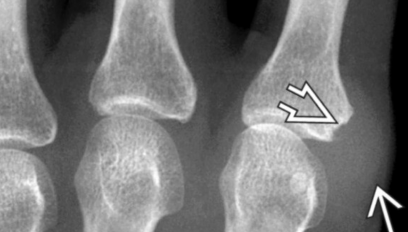

Pieds

- Erosion de l’aspect latéral de la 5e MTP++